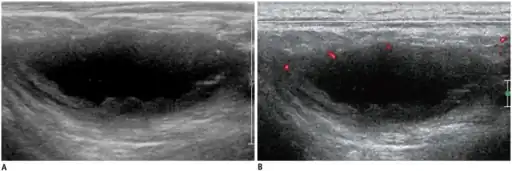

Diagnostic algorithm of chronic lymphadenopathy[12] -

a,b)Individual diagnosed with tuberculous lymphadenitis -ultrasonography/Doppler ultrasonography